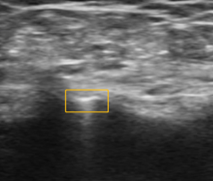

超声可见临时封堵盘贴合血管壁,胶原蛋白精准部署